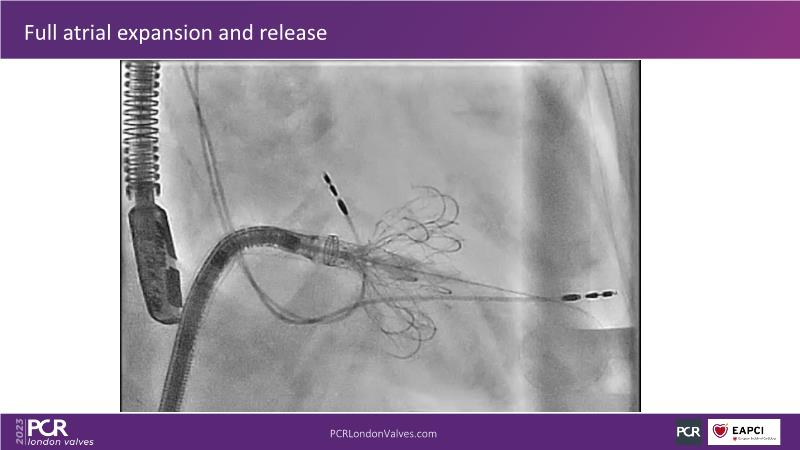

This session explores the features of the PASCAL Precision and the EVOQUE tricuspid replacement systems through simulators and case presentations, while a panel of experts discuss the technology, witnessing live demonstrations of treating mitral and tricuspid regurgitation patients.

- To introduce the EVOQUE tricuspid replacement system showcased with a simulator and a case presentation